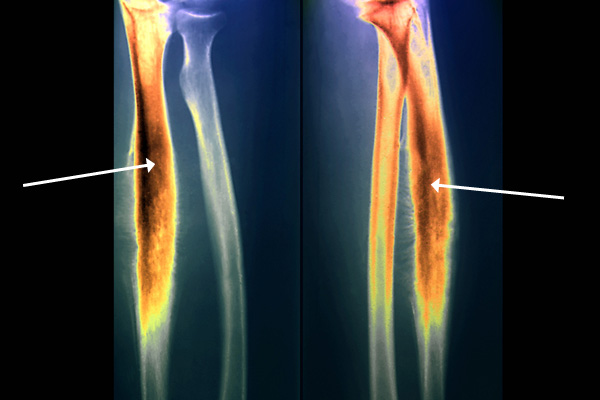

σάρκωμα EwingΧρωματιστή ακτινογραφία χεριού, όπου τονίζεται το σάρκωμα Ewing (πιο έντονα πορτοκαλί περιοχή)